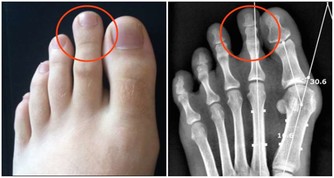

第二個就是腎虛

一般腎不好的人都會有早醒的情況,除了這個情況以外還會有腰膝發酸發軟的情況,有些人還會有眩暈的毛病,有些男性還有可能出現遺精的問題,一般這些症狀就是腎虛了。